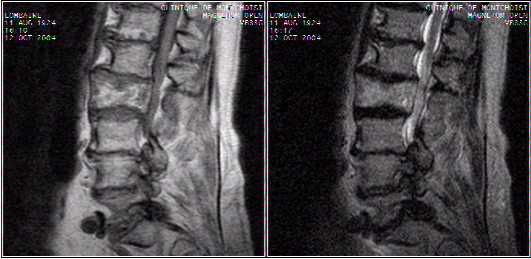

Spine cases